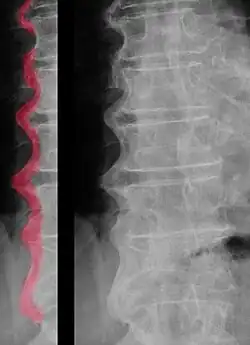

Morbus Forestier ist eine nach dem französischen Internisten Jacques Forestier (1890–1978) benannte, systemische, nichtentzündliche Skeletterkrankung, die auch Spondylosis hyperostotica und Zuckergusswirbelsäule[1] genannt wird. Charakteristisch ist eine Ossifikation der Enthesen, also jener Stellen am Knochen, an der eine Sehne, ein Ligament oder eine Gelenkkapsel ansetzen. Forestier und sein Schüler Jaume Rotes-Querol beschrieben die Erkrankung 1950 als „greisenhaft versteifende Hyperostose der Wirbelsäule“ (englisch senile ankylosing hyperostosis of the spine).[2] Vornehmlich bei älteren Patienten (auch bei Wirbeln vom Höhlenbären[3]) wurden knöcherne Anbauten an den Wirbelkörpern beobachtet, die im Verlauf immer mehr zunehmen und mit der Zeit zu einer Überbrückung der Bandscheibenräume führen. Da der Morbus Forestier große Abschnitte der Wirbelsäule befällt, geht er mit einer zunehmenden Versteifung der Wirbelsäule einher. Inzwischen ist bekannt, dass die Erkrankung weder auf die Wirbelsäule noch auf ältere Menschen beschränkt ist. 1976 prägten Donald R. Resnick und Gen Niwayama hierfür den Begriff Diffuse idiopathische Skeletthyperostose (kurz: DISH), welcher aktuell weit verbreitet ist.[4] Sie wiesen darauf hin, dass die Erkrankung schon 1942 vom Radiologen Albert Oppenheimer[5] beschrieben wurde.[6]

Die Diagnose einer DISH kann alleine auf Röntgennativaufnahmen gestellt werden. An den Wirbelkörpern sieht man im Röntgenbild einen meist rechtsseitigen zuckergussartigen Überzug von Knochenmaterial (Hyperostosen). Durch die Überbrückung der Bandscheibenräume ist die Beweglichkeit der Wirbelsäule in diesem Segment aufgehoben.